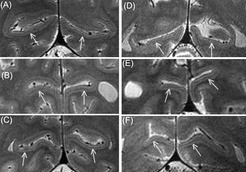

Der Gennari-Streifen (rechts bei sehenden Probanden, links bei blinden) zeigt sich im MRT als feine dunkle Linie in der um den Sulcus calcarinus (weiß) angeordneten primären Sehrinde. Zur eingriffslosen Untersuchung solcher extrem dünnen Strukturen am lebenden Menschen nutzen die Forscher einen Hochleistungs-Magnetresonanztomografen mit einer Feldstärke von 7 Tesla.

Auch im Gehirn von Geburt an blinder Menschen bildet sich in der Sehrinde der so genannte Gennari-Streifen und degeneriert trotz fehlender Sehinformation nicht. Das stellten Forscher um Robert Trampel vom Max-Planck-Institut für Kognitions- und Neurowissenschaften mit Hilfe der Magnetresonanztomografie fest. Der etwa 0,3 Millimeter dicke Strang von Nervenfasern ist demnach nicht nur für optische Informationen zuständig. Bei Blinden verarbeitet er möglicherweise in erhöhtem Maße taktile Reize. Das könnte zu einer Schärfung des Berührungssinns beitragen und etwa das schnelle Lesen von Braille-Schrift unterstützen. Der Gennari-Streifen durchzieht als gut sichtbare Linie die graue Substanz in der primären Sehrinde im visuellen Kortex des Gehirns. „Obwohl der visuelle Kortex zu den am meisten untersuchten Gebieten im Gehirn zählt, und der Gennari-Streifen eine recht auffällige Struktur ist, wurde bisher nie genauer erforscht, warum er sich bildet und was seine Funktion ist“, sagt Robert Trampel, Mitarbeiter der Abteilung Neurophysik am Max-Planck-Institut für Kognitions- und Neurowissenschaften.  „Vermutet wurde naheliegenderweise ein Zusammenhang mit dem Sehen“.